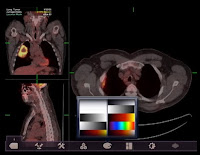

Um cliente PACS no seu iPAD. Você pode tentar conectar ao PACS através de um dekstop virtual o que o autoe conseguiu pelo Agfa IMPAX via Citrix (veja imagem abaixo).

![]() |

| Agfa IMPAX via Citrix |